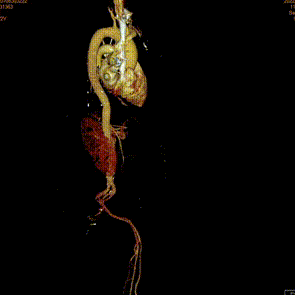

术后1w——冠脉CTA